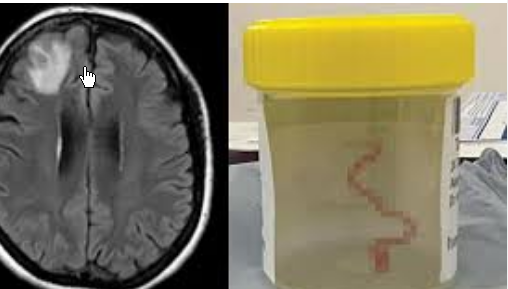

医院第五神经外科主任陆明医生在检查病人后,从影像资料中发现了一个关键线索:病灶不仅活动,而且还呈现出“隧道征”——这是寄生虫在脑内留下的痕迹。凭借多年清除寄生虫的经验,陆明医生相当肯定这是脑裂头蚴病。随后的血清检测显示裂头蚴抗体呈阳性。不久之后,卢明博士的团队进行了裂头蚴切除手术,成功取出了一条8厘米长的活虫。